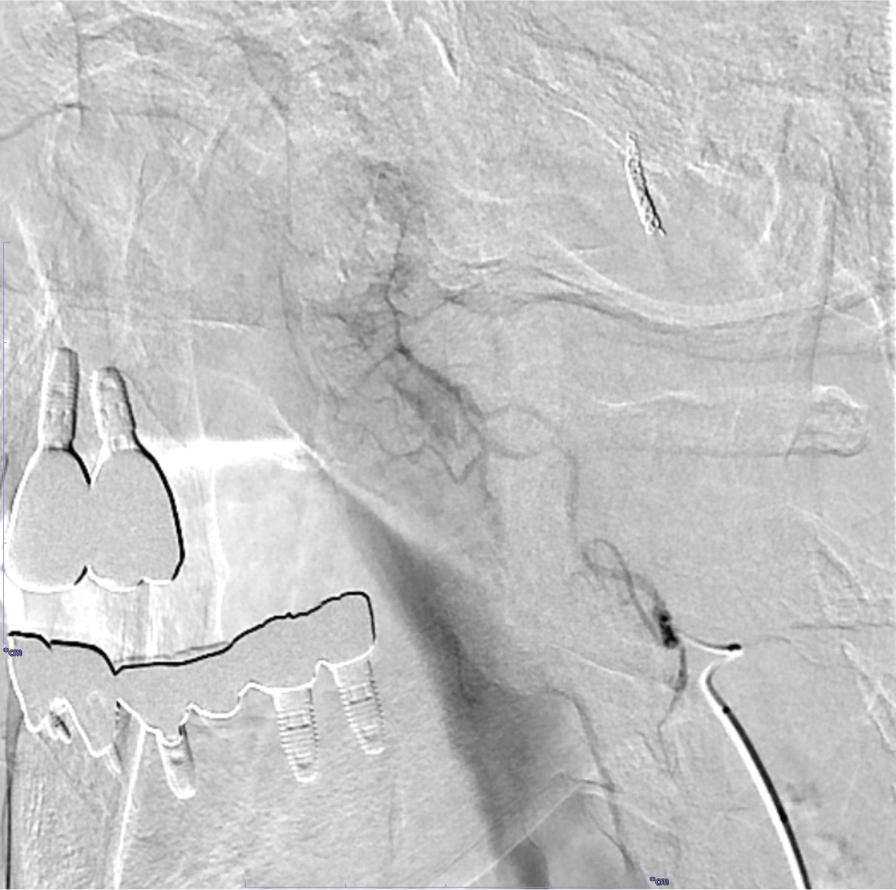

RADPLATは大量シスプラチンの超選択的動注化学療法と放射線治療の同時併用療法であり、局所制御の向上と臓器機能温存を期待できる。超選択的動注化学療法で癌の根治を目指す上で、腫瘍の進展範囲や栄養血管の同定、また周囲の重要構造物との関係やアクセスルートなど詳細な術前評価が不可欠であり、造影CTで解剖学的構造物を正確に描出することが求められる。

当院では撮像されたCT画像を元に3D画像解析システム「SYNAPSE VINCENT」を使用して治療対象となる血管を抽出し、ワークステーション上で支援画像を作成している。これにより直感的な解剖の理解を得られるだけでなく、放射線技師や看護師など手技に関わるスタッフと事前に情報共有することが容易になり、これもまた治療の有効性や安全性を高めることに寄与する。

画像再構成は腫瘍の位置や血管走行を詳細に評価するため、0.5mmにスライス厚を設定する。各動脈、腫瘍を色分けしたVR像なども血管造影の際の支援画像として重要である。